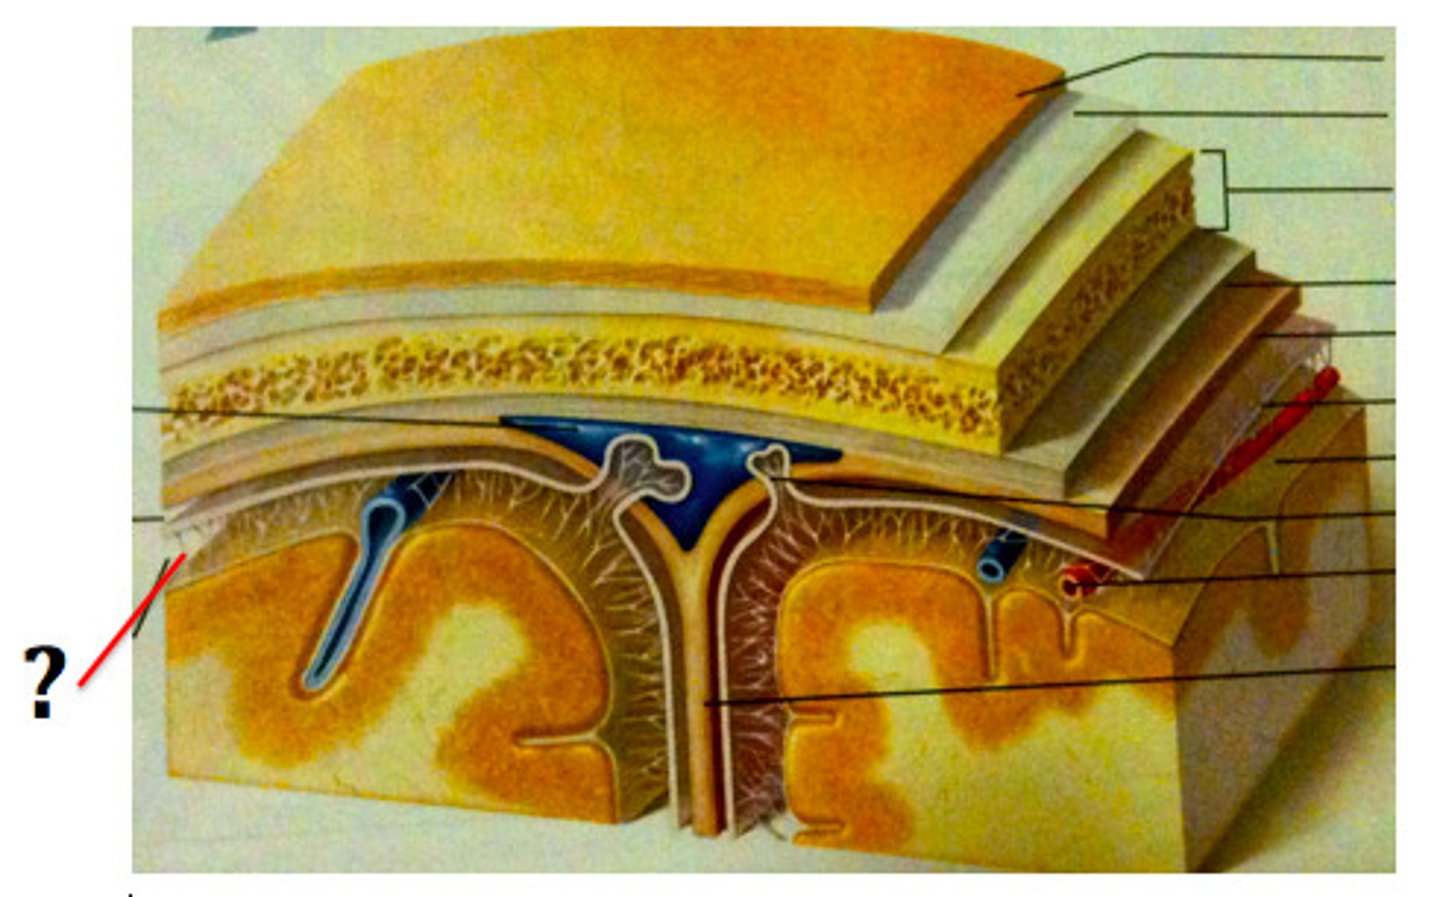

Ventricles

-Internal chambers within the brain

Lateral ventricles

-One in each cerebral hemispheres

-Interventricular foramen

Interventricular foramen

-Tiny pore that connects to third ventricle

Third ventricle

-Narrow medial space beneath corpus callosum

-Connects to cerebral aqueduct

Cerebral aqueduct

-Runs through midbrain and connects to third and fourth ventricles

Fourth ventricle

-Small triangular chamber between pons and cerebellum

-Connects to central canal that runs through spinal cord

Choroid plexus

-Spongy mass of blood capillaries on the floor of each ventricle

Ependymal

-Type of neuroglia that lines ventricles and covers choroid plexus

-Produces CSF

Cerebrospinal fluid

-CSF

-Clear, colorless liquid that fills the ventricles and canals of CNS

-Bathes its external surface

CSF production

-Brain produces and absorbs 500 mL/day

-100-160 present at one time

-produced 40% in subarachnoid space

-Produced evenly by ependymal cells lining ventricles and by the choroid plexuses